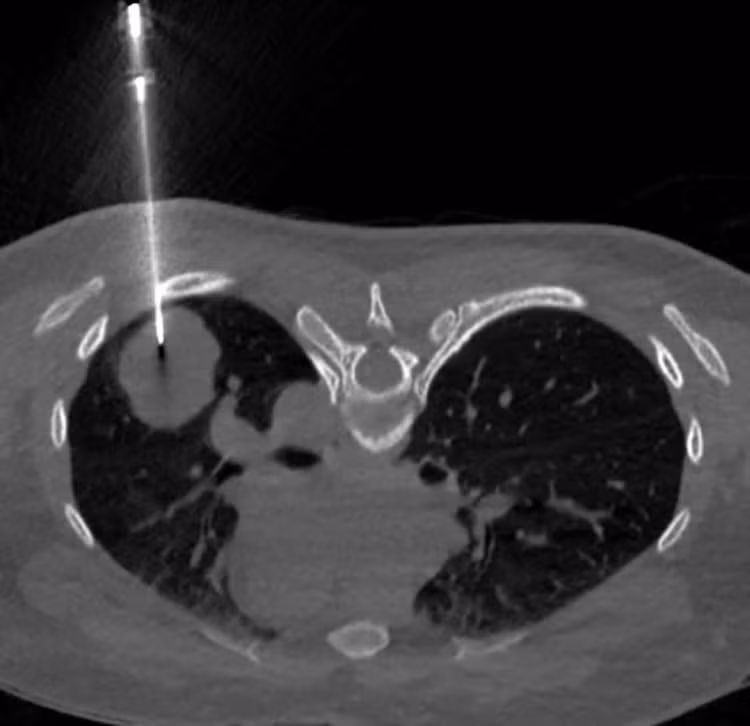

Nhận định đây là ca bệnh phức tạp, không điển hình, PGS. Phượng đã chỉ định sinh thiết phổi dưới hướng dẫn CT để xác định bản chất tổn thương.

BSCKI. Trần Văn Thụ - Trưởng Khoa Chẩn đoán hình ảnh, Bệnh viện Đa khoa Medlatec là người trực tiếp thực hiện sinh thiết cho bệnh nhân.

Hình ảnh sinh thiết phổi dưới hướng dẫn CT/Ảnh Medlatec